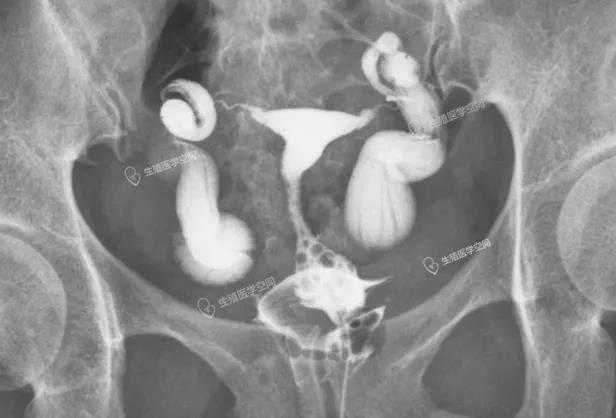

图7:右侧2个基本并联弹簧圈,左侧3个串联部分并联弹簧圈